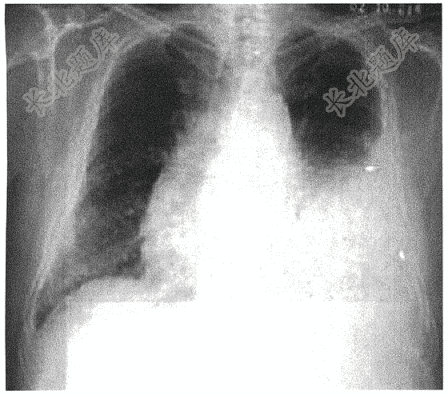

- 简答题患者,男性,30岁,咳嗽2月,胸闷、胸痛7天,请结合患者病情,读取相应影像学检查,并答出X线检查类型、投照体位、征象以及诊断